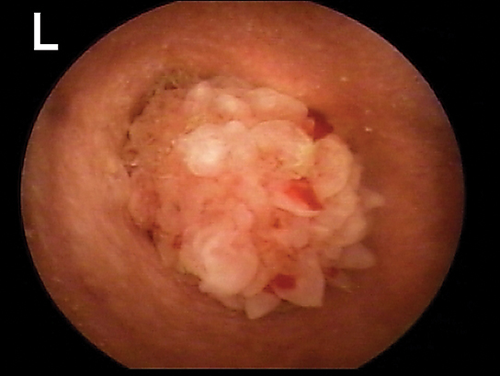

Any change in the epidermis, such as with ceruminous gland hyperplasia or ulceration, is significant and should be noted (Figure 4). In a patient with inflammatory ear disease, thickening of the epithelium may obscure visualization of blood vessels. The clinician should assess for presence of stenosis. Some dog breeds (eg, shar-peis, pugs) have small-diameter ear canals as part of their standard conformation. Differentiation between swelling and stenosis is necessary. Stenosis results from permanent pathologic changes within the epidermis of the ear canal (Figure 5).

FIGURE 4

Cerumen gland hyperplasia. Inflammation in the ear canal results in increased secretions from the apocrine glands, which enlarge above the epithelial surface.

For swelling of the ear canal caused by inflammation, it may be necessary to delay a complete examination of the ear canal until anti-inflammatory therapy (eg, systemic or topical corticosteroids) decreases the swelling.

If changes do not reverse, the prognosis for medical management is poor, and total ear canal ablation and/or bulla osteotomy is recommended. If the ear canal epithelium is smooth and pink in color but the ear canal diameter is narrowed, hyperplasia of the sebaceous glands may be present.